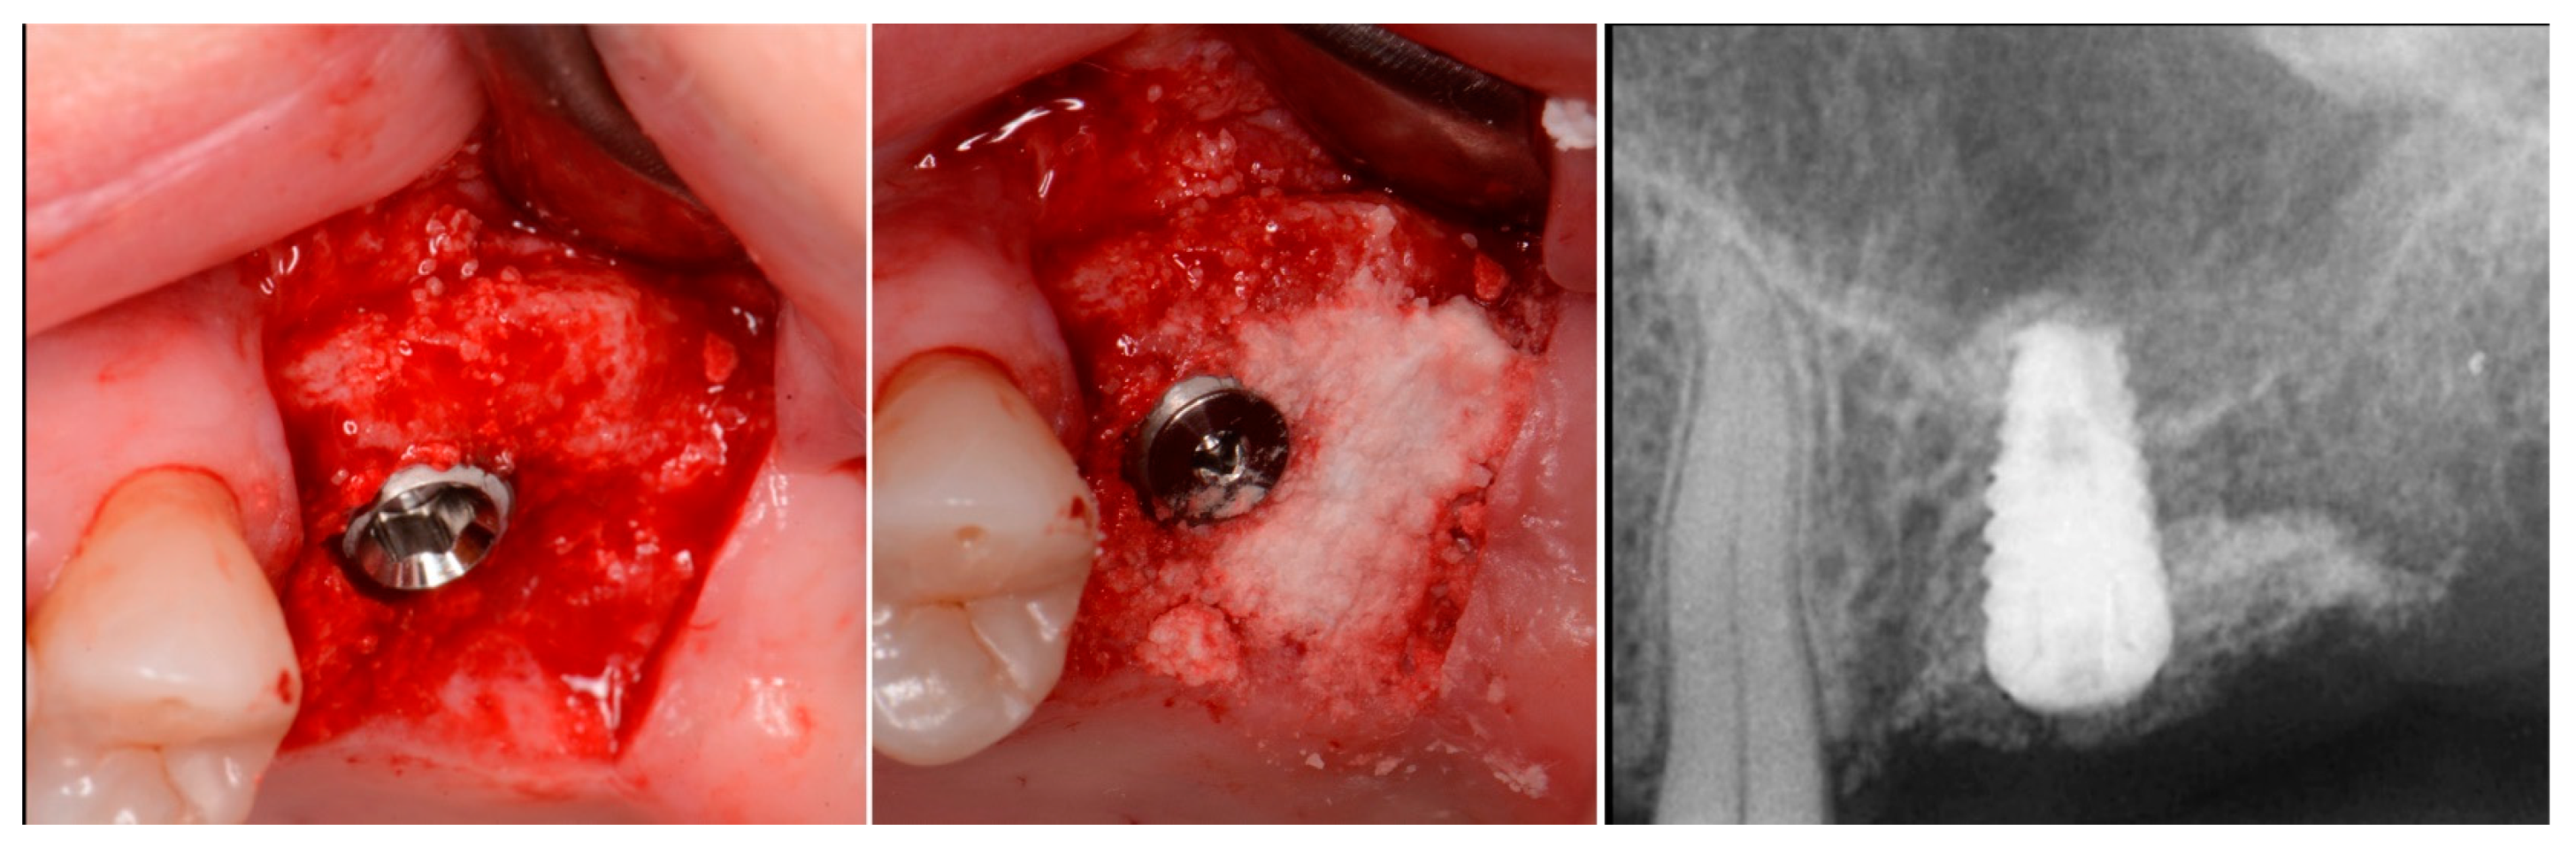

The patient returned at 10 weeks post-surgery and a periapical radiograph was obtained to evaluate the graft healing (Figure 1, right). The graft was noted to have blended with the surrounding host bone and was deemed ready for implant placement. The soft tissue covering the grafted portion of the ridge was keratinized and no inflammation was noted (Figure 2). Local anesthetic was again administered in a similar manner as the previous surgery. A crestal incision was made from the distal of the distal papilla at the 2nd premolar to a point where the 1st molar would be positioned. A releasing incision was made at the distal of the papilla and also at the posterior extent of the crestal incision and extended into the buccal vestibule. A full-thickness flap was elevated to expose the crestal ridge (Figure 3). The graft had converted to bone at the extraction sockets. A pilot drill was utilized to start the osteotomy to a depth of 4 mm, 2 mm shy of the sinus floor as measured on the radiograph. The osteotomy was increased laterally utilizing Densah osseodensification burs (Versah, Jackson, MI, USA) to a width of 4 mm (Figure 4, left). EthOss graft material that had been hydrated in the syringe was dispensed into the osteotomy and the final Densah bur was utilized to elevate the sinus floor and laterally spread the graft material to gain height for the implant placement (Figure 4, right). A 5 mm × 8 mm Paltop Addvanced (Paltop, Cesarea, Israel) implant was introduced into the site to the desired crestal depth (Figure 5, left). A cover screw was placed, and additional EthOss graft material was placed at the crest to fill a depression on the distal aspect adjacent to the implant (Figure 5, middle). A periapical radiograph was obtained to document the implant and associated sinus/crestal grafting performed at this stage (Figure 5, right).

Figure 5.

Implant placement into the crestally elevated sinus site (left), additional EthOss graft material to fill a crestal concavity (middle) and a radiograph following implant placement and flap closure (right).